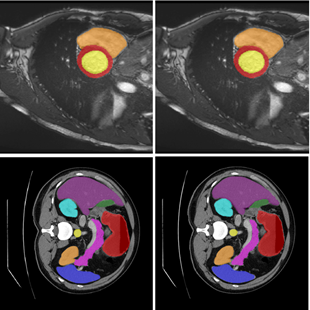

Medical Image Segmentation Transformer with Convolutional Attention Mixing (CAM) Decoder

Summary: One of the familiar and promising deep learning approaches used for medical image segmentation is transformers, as they can capture long-range dependencies among the pixels by utilizing self-attention. Despite being successful in medical image segmentation, transformers need help in capturing local contexts of pixels in multimodal dimensions. Hence, we are developing lightweight transformers with memory-enabled decoders and attention-mixing decoders for precise medical image segmentation. Github